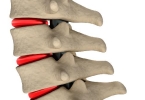

• 腰椎间盘突出症会影响到哪些部位

腰椎间盘突出症会影响到哪些部位

腰椎间盘突出症可能影响腰部、下肢及会阴区域,典型症状包括腰痛、坐骨神经痛和下肢麻木。腰椎间盘突出症主要由椎间盘退变、外伤或长期劳损导致,突出物压迫神经根或脊髓时,可引发相应支配区域的放射性疼痛或功能障 ...